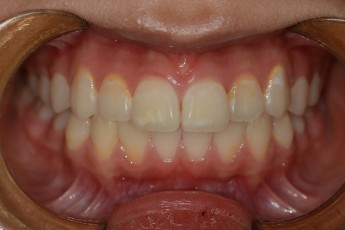

Before

After